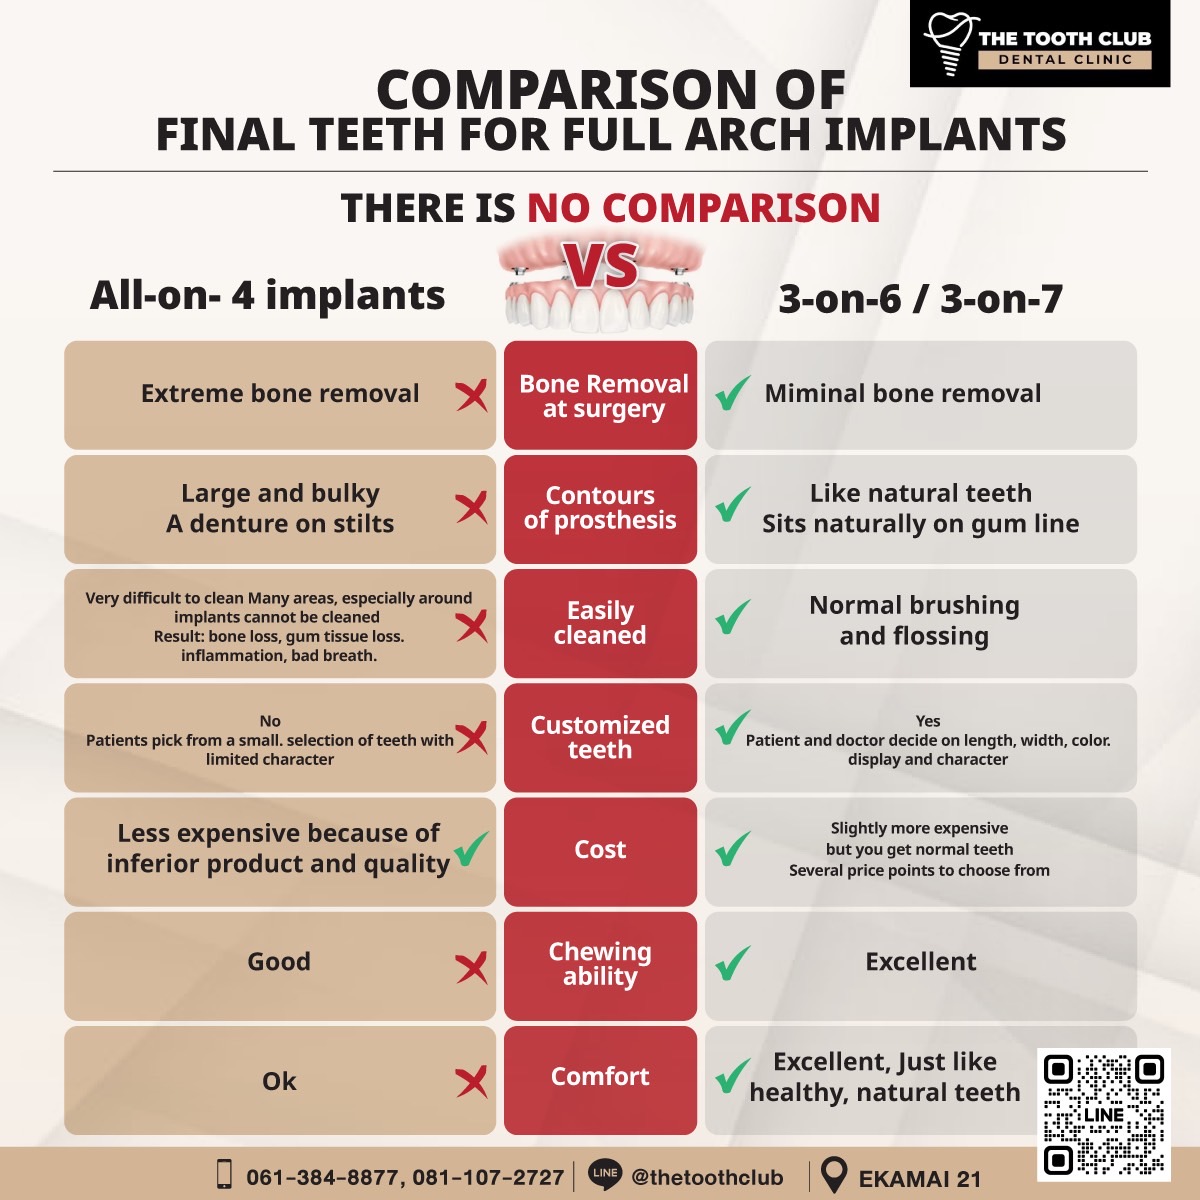

- All on 4

This procedure involves placing four implants in the jawbone to support a full set of fixed dentures or a bridge. It is perfect for those who have lost all their teeth in either the upper or lower jaw and want a secure, effective solution that performs better than removable dentures.